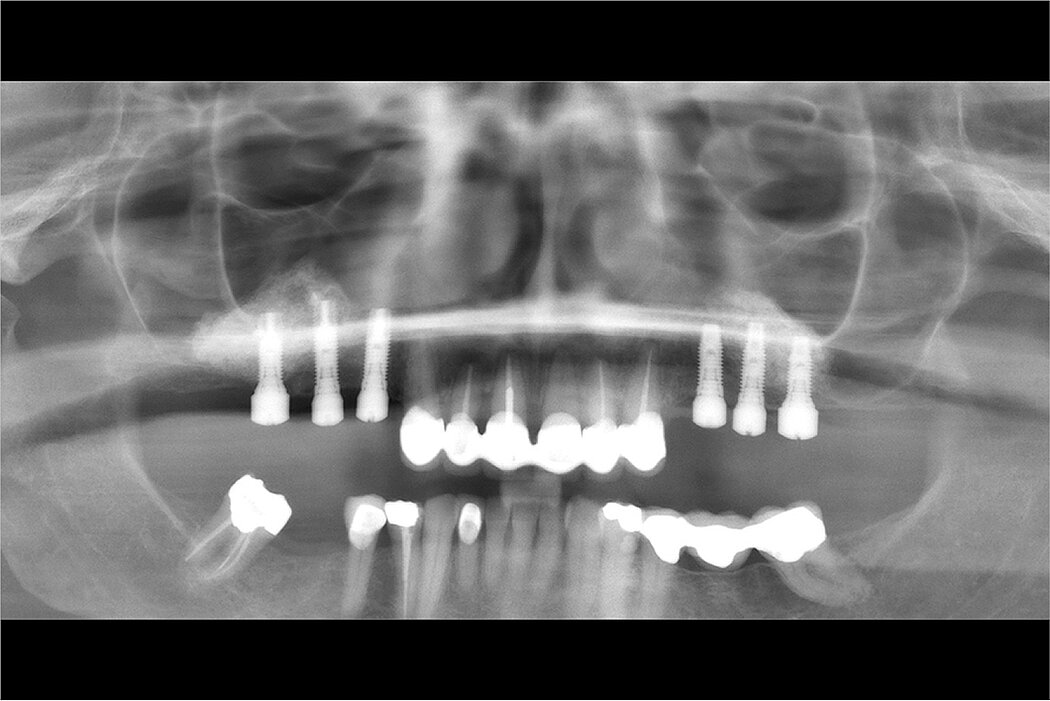

一名上颌牙保留无望的63岁女性患者,渴望进行固定修复。设计了分阶段的方案,将尖牙用作临时固位基牙,同时完成上颌窦底增量,分阶段植入种植体。该病例表现为在磨

牙部位有1-2mm的牙槽骨。在上颌窦底增量手术期间,右侧薄的上颌窦膜被大面积撕裂。使用胶原膜修复,单独使用Geistlich Bio-Oss®填充,并用Geistlich Bio-Gide®膜覆盖侧壁开窗来完成双侧窦底增量。经过较长时间的等待(经济原因)后,将种植体植入增量的上颌窦内,并采集骨样本。拔掉前牙并将临时牙冠延伸至后部种植体。随后将种植体植入尖牙部位,修复体最终制作完成。上颌窦底增量手术后随访长达13年。